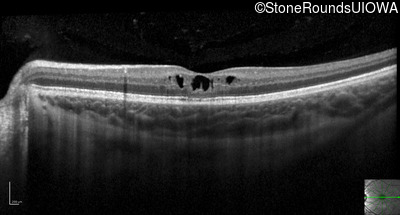

Optical Coherence Tomography - Right - 20/40 -2

Exemplar / OCT Stack